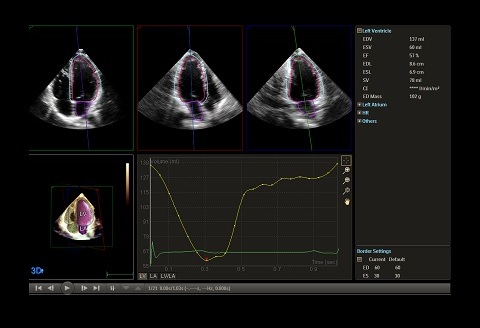

Dynamic HeartModel

取得した心臓3Dデータから、自動で心臓の駆出率(EF)を算出し、手動での計測と比較して最大82%の時間短縮を実現します。